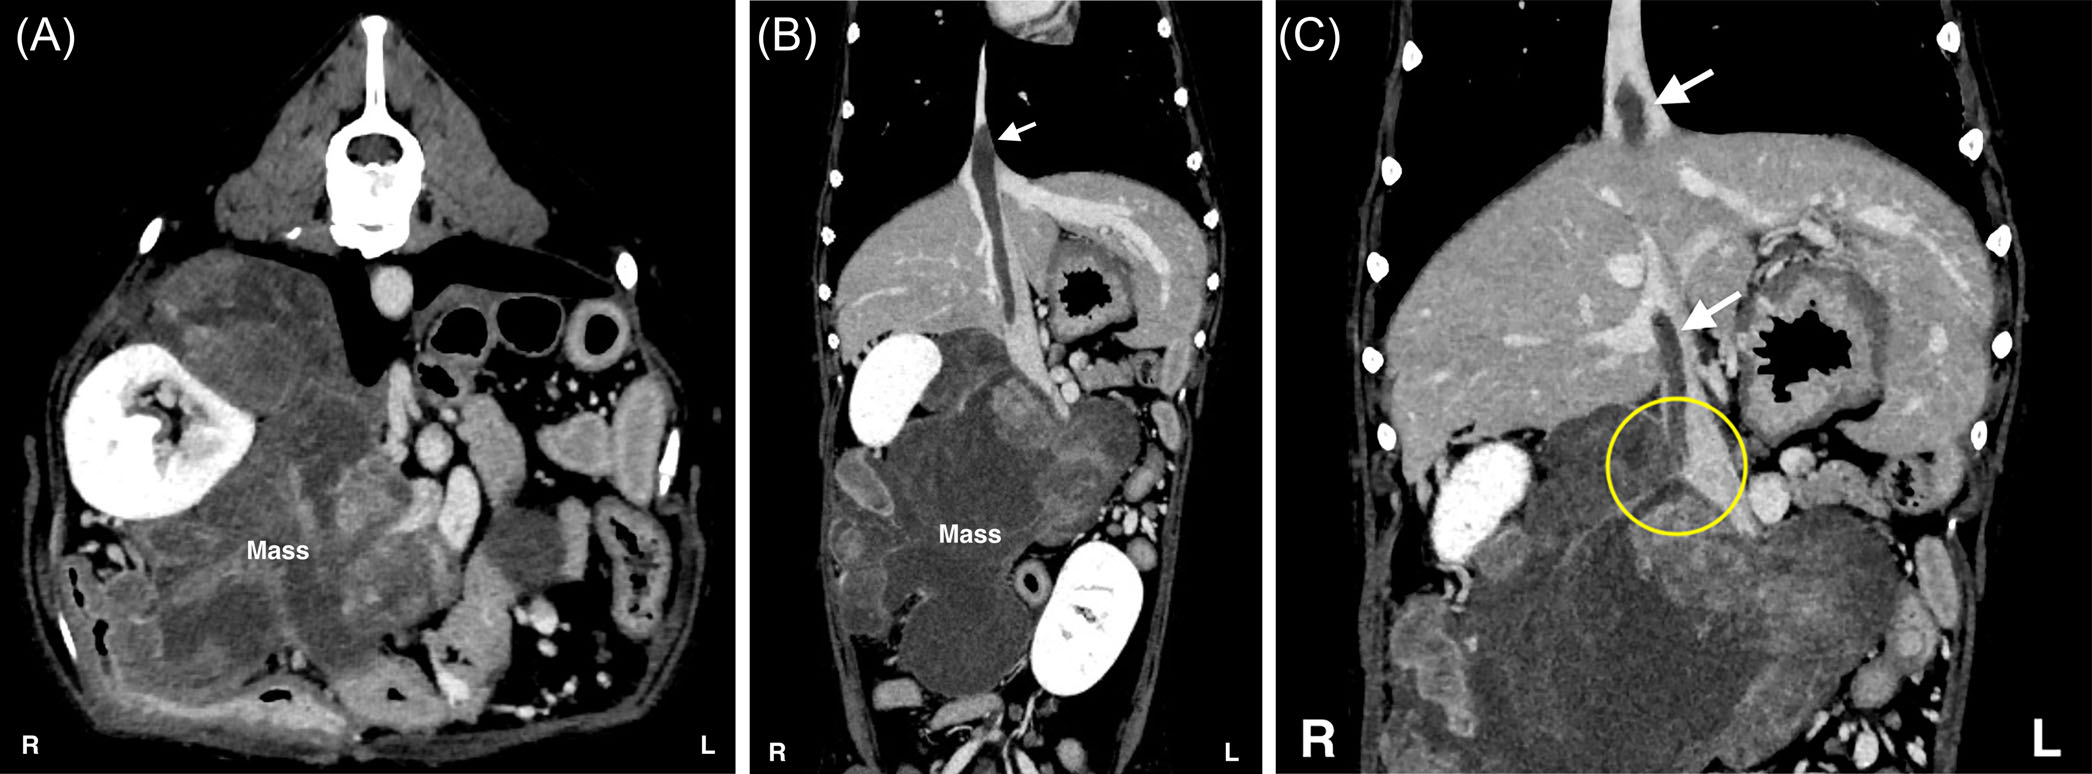

CT显示一个直径约15厘米的巨大肿块,从肝脏的尾侧压迫腔静脉,并影响右肾、右肾动脉和静脉(下图)。右侧肾上腺未被识别。CT血管造影显示肿瘤内部对比度增强较低,三相增强CT未见明显变化。还发现一个从右侧膈下腹静脉附近延伸至膈肌以上胸腔腔静脉的腔静脉血栓。

↑ 术前CT结果。(A)轴位图像。(B)冠状位图像。(C)冠状位图像突出显示腔静脉血栓的起源。在右侧肾上腺区域观察到一个巨大的肿块,从肝脏的尾侧压迫腔静脉,并累及右肾、右肾动脉和静脉。右侧肾上腺无法识别。肿瘤在CT血管造影中表现为低对比度增强,三相增强CT未见明显变化。腔静脉血栓(白箭头)起源于右侧膈下腹静脉(黄圈),并向头侧延伸至膈肌以上进入胸腔腔静脉。